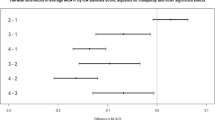

GTI was higher in patients with large-artery atherosclerotic stroke than in those with non-large artery atherosclerotic stroke (0.13 ± 1.09 vs. − 0.04 ± 0.96), although this difference was not statistically significant (P-value = 0.08). Similarly, GTI was slightly higher in patients with coronary artery disease (0.18 ± 1.18 vs. − 0.02 ± 0.97; P-value = 0.153) and peripheral artery disease (0.53 ± 0.0.84 vs. − 0.01 ± 1.0; P-value = 0.195), but these differences were also not statistically significant. GTI increased in a dose-dependent manner with the number of ICAS (Fig. 3). GTI was significantly higher in the high ICAS group than in the low ICAS or no ICAS group (no ICAS, − 0.12 ± 0.93; low ICAS, − 0.02 ± 0.97; high ICAS, 0.33 ± 1.16; P < 0.001). This trend was also confirmed in GTIb, with the difference in tortuosity index between groups being greater in GTIb (no ICAS, − 0.18 ± 0.91; low ICAS, − 0.04 ± 0.93; high ICAS, 0.52 ± 1.15). Looking at the curvaturem of each vessel, TI of both ICAs, right basal MCA, BA, right basal PCA, and right CbllA were higher in the high ICAS group than in the no ICAS and low ICAS groups, similar to the GTI (Table 2). Standardized aream was slightly higher in the high ICAS group than in the no ICAS and low ICAS groups (no ICAS, − 0.04 ± 0.89; low ICAS, 0.01 ± 0.85; high ICAS, 0.08 ± 1.40; P = 0.613). However, this was not statistically significant.

Distribution of global tortuosity index (GTI) and basal artery GTI (GTIb) values according to the number of stenoses in the intracranial arteries, plotted as a restricted cubic spline curve. The x-axis represents the number of stenoses in the intracranial arteries, while the y-axis displays the GTI values. Colored areas represent 95% confidence intervals.